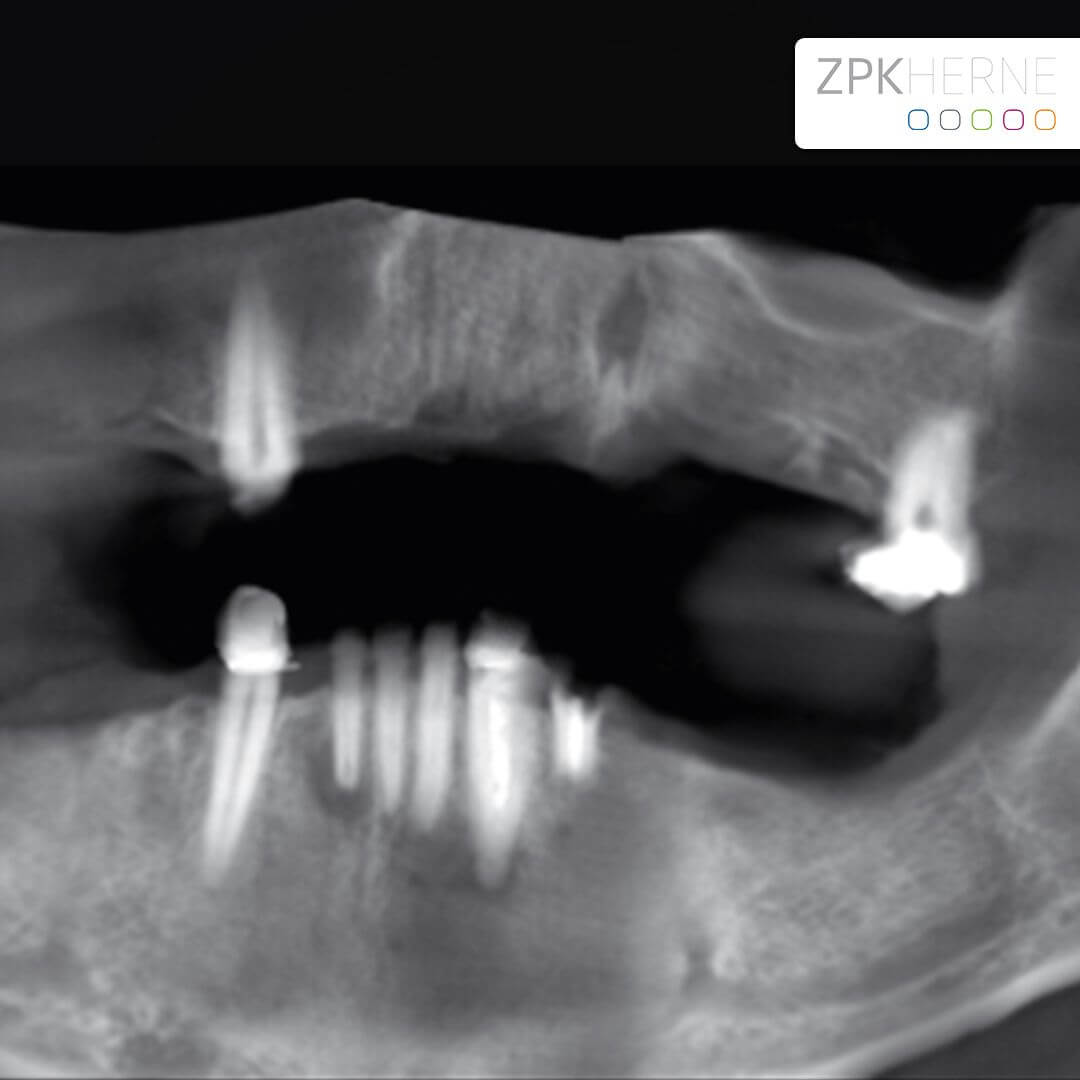

Ermittlung des Status Quo und schrittweise Planung

Bevor an einen operativen Eingriff gedacht werden kann, stehen als erstes Röntgenbilder mithilfe der Digitalen Volumentomographie auf dem Programm. Hier sind die Überreste in Ober-und Unterkiefer gut zu sehen, vor allem aber die Positionen der abgebrochenen Zahnwurzeln. Auf Basis der Bilder können die Positionen für die insgesamt 8 Implantate auf den Millimeter genau geplant werden: Unser Patient wird jeweils 4 Implantate im Ober-und Unterkiefer erhalten, die im Nachgang jeweils mit einem festsitzenden Zahnersatz versorgt werden. Die Einheilphase dauert zwischen 4 und 6 Monate, prognostiziert Dr. Mintert, der Spezialist für Implantate in der ZPK Herne.

Röntgenbild Kiefer - vor OP

Implantatplanung - Oberkiefer - All-on-Four Konzept

Implantatplanung - Unterkiefer - All-on-Four Konzept

Herzstück des All-on-4 / 6 – Behandlungskonzepts mit Camfour™ ist die aufwendige 3D-basierte Diagnostik. Diese findet im Vorfeld der eigentlichen Zahnimplantation statt. Mit Hilfe von dreidimensionalen DVT-Röntgenaufnahmen und der hochmodernen SIMPLANT®-Software macht sich unser Experte für Implantologie, Dr. Mintert ein detailgenaues Bild von Ihrem Kiefer. Dabei interessieren ihn nicht nur das verfügbare Knochenvolumen, sondern auch die empfindlichen Strukturen des Kiefers, die Knochenqualität und der umliegenden Bereiche. Hierzu gehört neben der Kieferhöhle auch Ihr Unterkiefernerv, auf den wir beim Implantationsvorgang besonders achtgeben müssen. Mithilfe der 3D-Diagnostik kann der Zahnarzt auch feststellen, ob All-on-four/six überhaupt für Sie geeignet ist.

implantat unterkiefer 3d

3d Diagnostik Röntgenbild

Unter Einsatz der SIMPLANT® Planungssoftware kann der Implantolgoe die optimalen Implantatpositionen vorab am Computer planen, wobei sämtliche Planungsdaten anschließend in die Herstellung einer individuellen Bohrschablone einfließen. Die Bohrschablone ermöglicht ein punktgenaues, schonendes Einsetzen der Implantate an den zuvor geplanten Positionen, minimiert das Verletzungsrisiko und beschleunigt letztendlich die Heilung.